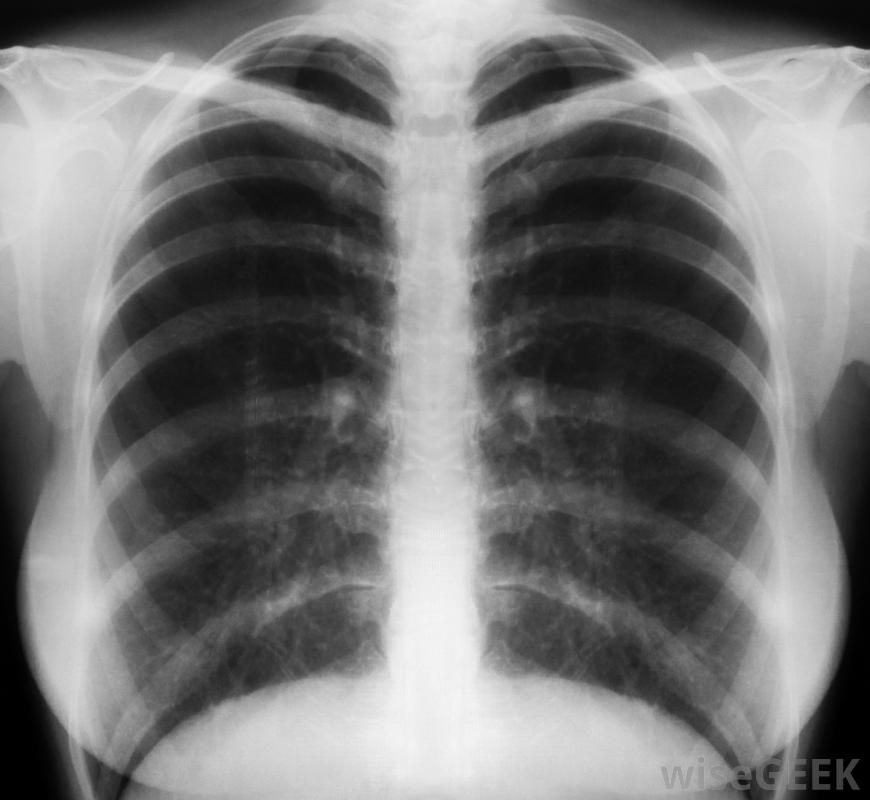

在x光片上很容易漏掉肩胛骨骨折。车祸是肩胛骨骨折最常见的原因之一,虽然其他原因也有可能,但由于骨骼得到了很好的保护,所以造成肩胛骨骨折所需的力必须相当大。肩胛骨骨折的人通常会有其他更严重的损伤,需要注意,这有时意味着骨折可以不被诊断,患者很可能会在患处感到疼痛和压痛,他或她会注意到肩膀和手臂的活动性降低,他或她在移动手臂或肩膀时也会听到研磨的声音,这是由于生骨端互相摩擦造成的。肿胀和瘀伤都会发生,尤其是肩胛骨骨折是直接外伤造成的肩胛骨也被称为肩胛骨,连接锁骨和上臂。一旦诊断出来,手臂和肩部必须固定以使骨骼自行愈合一旦愈合,很可能需要物理治疗。一些小的骨折会很快愈合,而更严重的骨折则需要较长的恢复时间。最严重的骨折可能需要手术,允许医生用别针或其他矫形器修复骨骼,尽管这对肩胛骨骨折。胸部x光检查通常是对因严重撞击而导致胸部或背部疼痛的患者进行的,即使是x光检查,也很容易漏掉肩胛骨骨折。这并不是因为因为肩胛骨的大部分骨折都很小,可以自行愈合,疼痛管理,如止痛药和制动将有助于愈合过程,并应在受伤后一两周内进行轻度活动训练